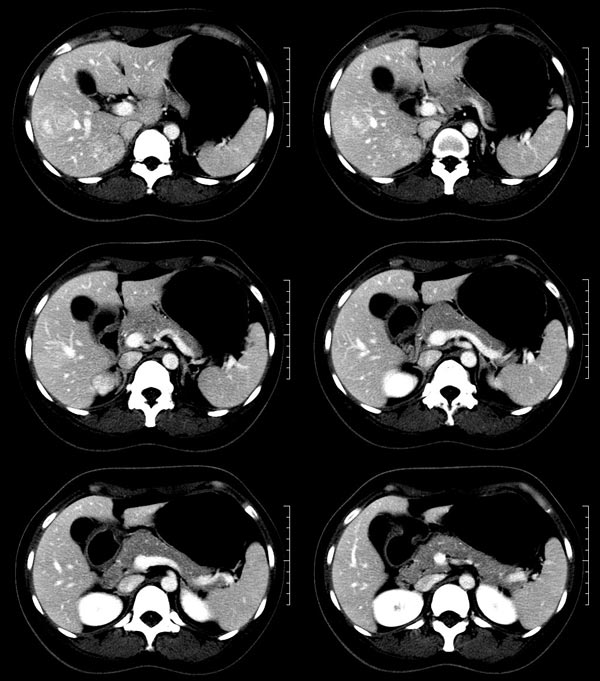

以下是引用52yingxiang在2007-9-16 10:16:00的发言:[br]肝脏局灶性结节增生影象表现(fnh)[br][br]肝脏局灶性结节增生是一种少见的肝脏良性肿瘤,可表现为边界清楚并无包膜的实质性肿块。病变大小不一,多系单发,亦可多发。组织学上是由结构紊乱的肝细胞、库普弗细胞、胆管、血管和粗厚的纤维性间隔所组成。[br]局灶性结节增生的ct表现可归纳为6点:[br]1、密度变化是其特征性改变,平扫多为低密度,少数为等密度,无论增强的早期或晚期均可能呈等密度,增强扫描有助于发现平扫为等密度的病灶;[br]2、中心疤痕,部分病灶在动态ct扫描时早期可看到中心疤痕增生性结节性病灶,ct血管造影也可看到普通ct不能显示的车轮状血管和车轴样改变;[br]3、纤维性分隔影,平扫为低密度,增强后为高密度;[br]4、包膜征象,增强后可以出现包膜强化,晚期较明显;[br]5、邻近血管的改变,主要是肝静脉受压,是发现等密度病变的重要依据;[br]6、瘤内胆管显影,这需要在胆管造影增强的情况下方能显示,出现率不高。[br][br]本例特点: 平扫低密度,增强动脉期明显强化,中心点条状低密度影(考虑纤维瘢痕),静脉期及延时期明显退减并与肝呈等密度,但中心仍可见低密度灶。[br]考虑肝脏局灶性结节增生(fnh)